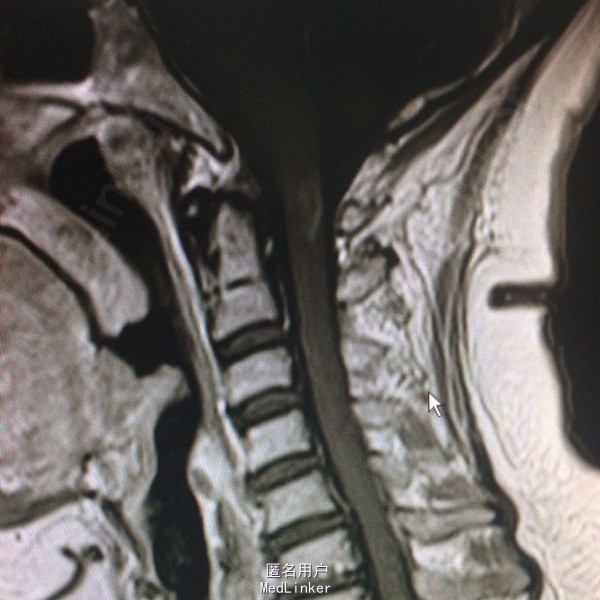

查体:左侧上肢、左侧颈项部、左侧躯干浅感觉减退,左上肢有力5-级,左侧肢体腱反射(+),余(-)。 辅助检查:头颅CT:右侧顶叶、左侧岛叶少许腔隙性梗塞,侧脑室旁脑白质变性,脑萎缩。 入院后查风湿三项:RF:74IU/ml,肌酣:92umol/L。尿酸:362umol/L,胆固醇:6.44mmol/L。糖耐量试验正常。输血四项正常。血沉、自免八项、血管炎3项、血找狼疮细胞均正常。心脏彩超正常。椎动脉彩超、颈动脉彩超正常。肌电图:左侧正中神经腕部节段性损害(感觉纤维受累,脱髓鞘改变),符合左侧腕管综合征电生理改变;左侧正中神经、左侧尺神经F波异常,提示近端神经根(C8-T1)受累,请结合临床。头颅MR:双侧额叶皮层下多发小缺血变性灶,未见急性梗死;右侧椎动脉颅内段较左侧明显细小,颅脑MRA未见异常;右侧桥小脑角增宽,未除蛛网膜囊肿。颈椎MR:颈椎轻度后弓,退行性变:C2/3、C3/4、C4/5、C5/6椎间盘突出(后正中型);C6/7椎间盘膨出,C1椎体水平脊髓内异常信号影,建议增强扫描。增强扫描示:C1水平脊髓内异常信号,脊髓炎与多发性硬化相鉴别。

诊断:急性脊髓炎。 治疗经过:入院后予B1、甲钴胺营养神经,患者症状稍有好转,在完善颈椎MR后考虑急性脊髓炎,予激素冲击治疗。